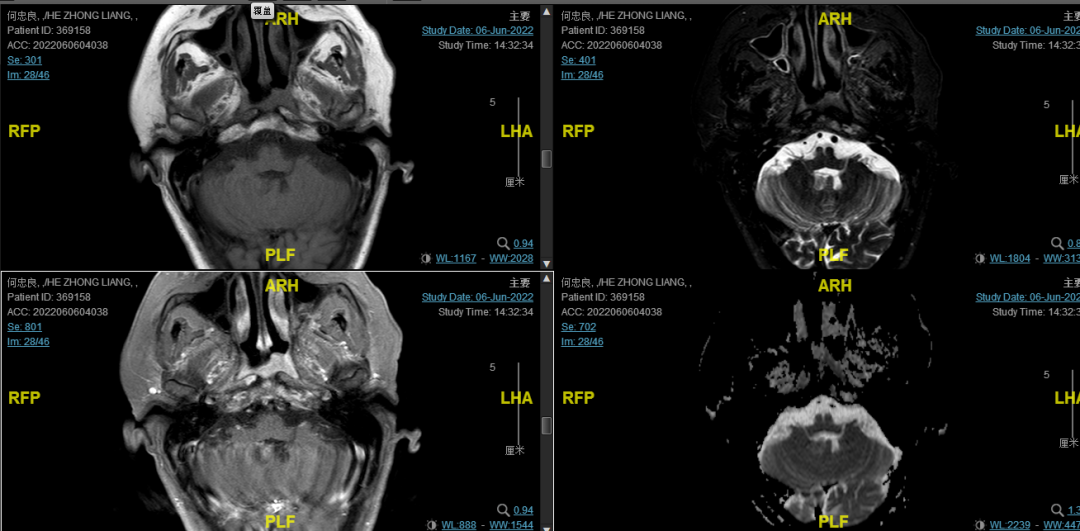

后患者至江苏省肿瘤医院放疗科就诊,2022-06-06完善头颅MR检查:

修正诊断:鼻咽癌T3N1M0,Ⅲ期。